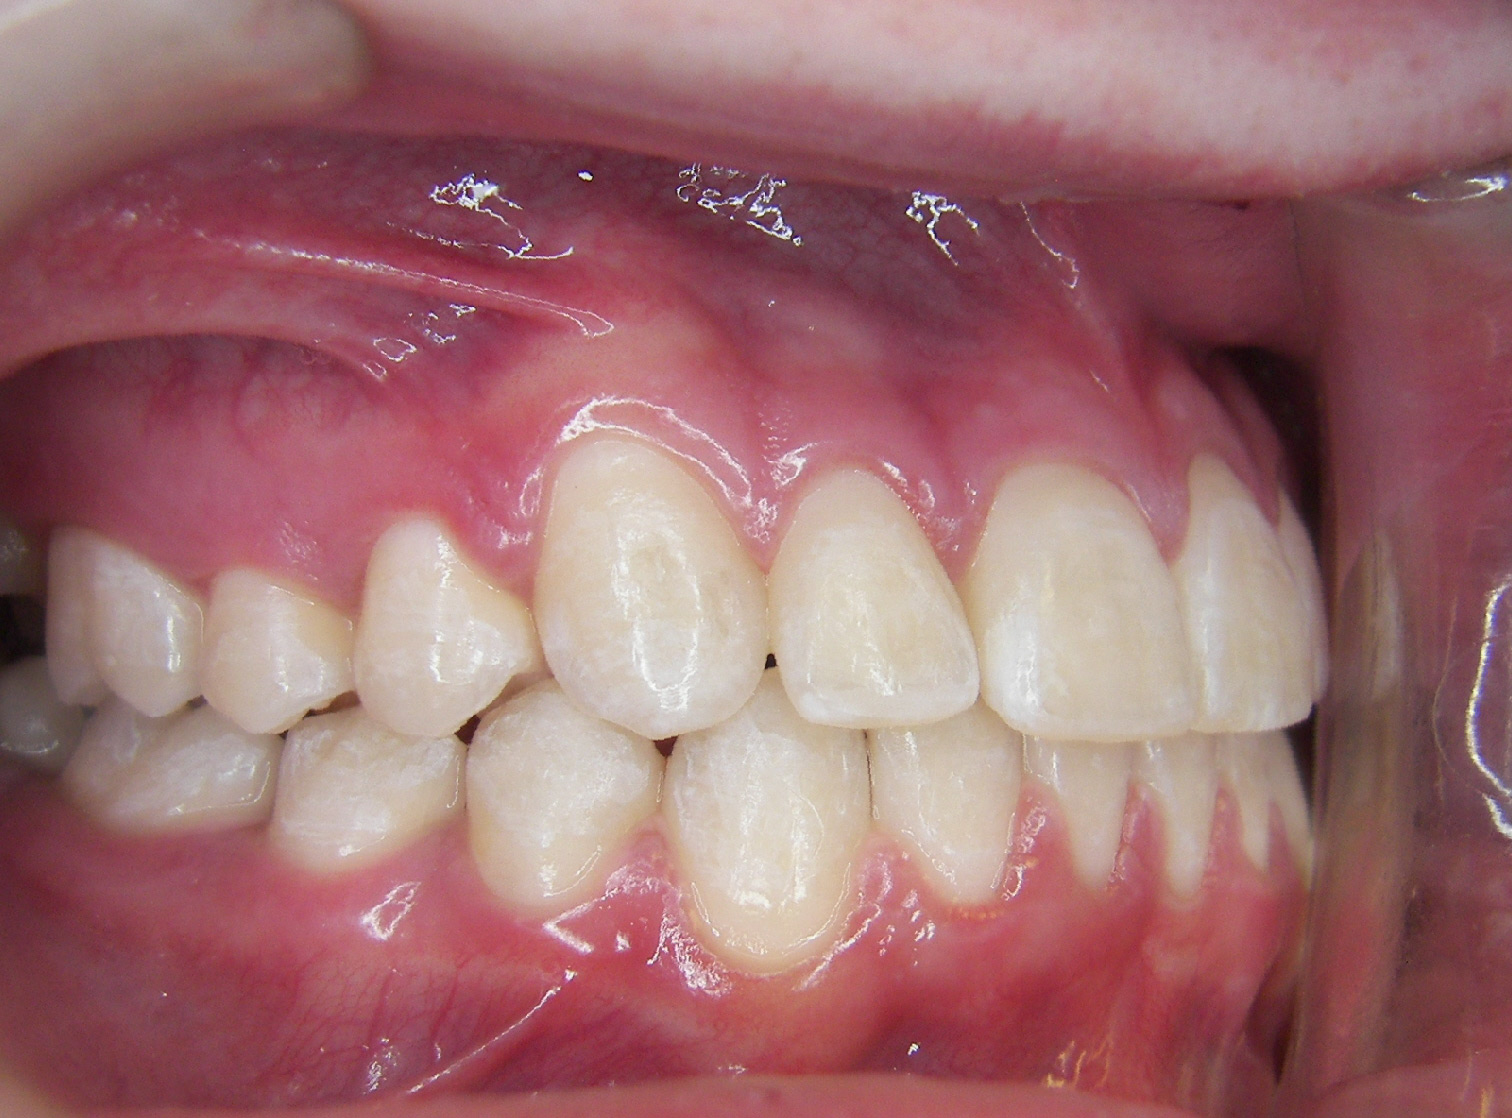

Case Studies

We’re proud of our patients’ new smiles, and most times, they’re even more proud to show them off. You’ll be ready for your close-up, too, once you visit the friendly experts at LB Orthodontics. Click here to see our smile gallery.

The American Association of Orthodontists (AAO) recommends that all children be seen by an orthodontist for evaluation by age 7 or 8. Please call us today to book your complimentary consultation.